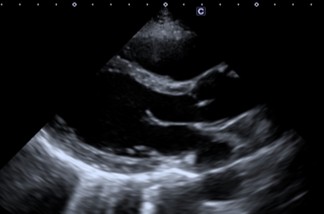

心臓超音波検査

心臓超音波検査は、心臓のリアルタイムの動きを観察することが出来ます。超音波検査の優れた点は、このリアルタイム、専門的に言い換えれば時間分解能が高い点と非常に安全かつ簡便に施行できる点になります。心エコー検査は、心臓の大きさや動き、壁の厚さ(心肥大の診断に用います)を計測することが可能です。

その中で心臓の動き(壁運動評価)は、心エコー検査の中でも、熟練が必要だと言われてます。また読影する人によりばらつきが生じることもあります。

AI技術を用いて自動でEF(左室駆出率)を算出する機能と同時に、詳細な壁運動の指標をカラーマップで提示でき、収縮のタイミングもグラフで確認可能となり詳細な解析が可能となります。